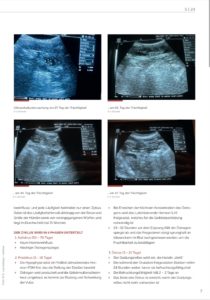

Hebamme für Hunde – Begleitung während Trächtigkeit und Geburt

Veröffentlicht im „mein Tierheilpraktiker“ – Ausgabe 05/2024

Hebamme für Hunde THP 5_2024 (PDF)